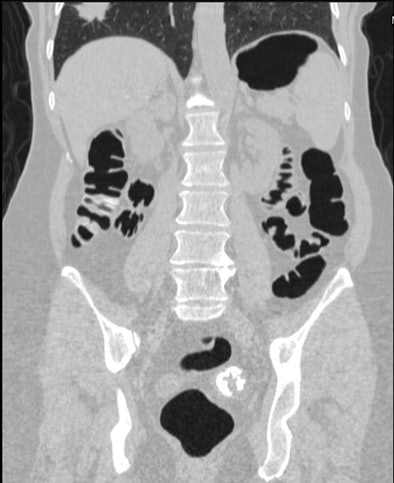

| Coronal image shows unsuspected cancer (partially imaged spiculated mass) involving the right lung. All images courtesy of Dr. Perry Pickhardt. |

As for extracolonic lesions, the mean patient age (61.3 years) was similar to the general cohort, and gender (19 women, 17 men) did not differ greatly from the entire group. The most common extracolonic primary cancers were renal cell carcinoma (n = 11, including 10 stage I), followed by lung cancer (n = 8, including three stage I, one stage II, three stage II) and non-Hodgkin's lymphoma (n = 6). In addition, two patients had prostate cancer and two had localized adrenal cancers. Some of the other cancers detected included a breast cancer, a stromal cancer in the stomach, a carcinoid tumor in the appendix, and a stage I adrenocortical carcinoma.

Virtual colonoscopy provides a limited view of extracolonic regions including the abdomen, pelvis, and parts of the lungs, and additional diagnostic tests are required in about 6% of cases, "nearly half of which ultimately prove to be clinically relevant," Pickhardt said in his statement. Of note, the study found no presymptomatic pancreatic or ovarian cancers. As of the publication date, one patient with an unsuspected malignancy had died of apparently unrelated causes.